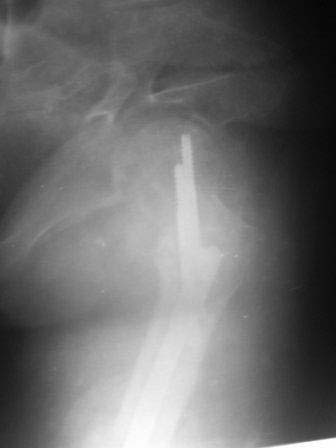

Уважаемые коллеги. Госпитализирован б-ной 47 лет, травма высотная 9 месяцев назад, тогда оперирован и/м остеосинтез (чрезвертельный перелом не диагностирован) в одном мед.объединение, через 3 месяца почему-то штифт удален. Больной ходит с двумя костылями, ногу не нагружает, выраженная патологическая подвижность в с/з бедра, в обл вертелов патологическую подвижность определить не удается, умеренная отечность всего бедра, укорочение около 4-5см. В плане в начале дистрактор, после устранения укорочение и репозиции БИОС реконструктивным стержнем( универсальным). Уважаемые коллеги помогите советом!, какие другие варианты, нюансы, случаи из практики! С уважением Абдурашид.

ЭОП унас нет, больной оперирован тогда, 35 дней назад, во время наркоза определена патологическая подвижность в вертельной обл, поэтому произведена остеотомия с исправлением угла, антеградный БИОС ,универсальный стержень ChM. Рентген снимки свежие фас и аксиальная. Пациент ходит с двумя костылями, ногу частично нагружает, лежа выпрямленную ногу поднимает.